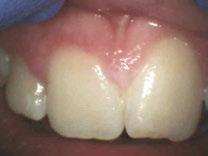

Dr. Bill Waggoner discusses the benefits of using liners along with a case presentation from Dr. Paul Bahn

Cavity liners and indirect pulp capping (IDPC) materials have been used in dentistry for decades. The recent introduction of NuSmile’s NeoLINER™ LC now provides one of the most therapeutic, easy-to-use liners on the market! It is a light-cured MTA-modified bioactive material that is recommended for use as either a cavity liner or as an indirect pulp-capping material. For decades, calcium hydroxide was the most popular lining or indirect pulp-capping material, primarily because of its ability to stimulate reparative dentin. However, its solubility after placement was found to be a problem. Zinc oxide and eugenol, glass ionomers, and resin-modified glass ionomers have also been used as liners, bases, and IDPC materials, but each has shortcomings.

Liners are materials that are placed in thin layers over exposed dentin in the deepest portion of cavity preparations. They function to seal dentin tubules, prevent microleakage, provide some thermal insulation, and depending on the material used, stimulate the formation of reparative or tertiary dentin. Historically, indirect pulp-capping materials have been used when a thin layer of carious dentin remains after deep excavation with no exposure of the pulp and no clinical signs of irreversible pulpitis. In recent years, indirect pulp capping in pediatric dentistry has been utilized when larger amounts of carious tissue remain, but the caries can be sufficiently sealed from the oral environment with a full coverage restoration like a stainless steel or zirconia crown. The main goal of both liners and IDPC materials is to minimize inflammation, promote healing, and maintain vitality of the dental pulp. Indirect pulp capping materials may also demonstrate some bactericidal properties to kill any remaining bacteria that may remain.

The MTA in NuSmile’s NeoLINER LC provides a continuous high calcium release. This, in combination with a high pH, promotes hydroxyapatite formation and protects against hypersensitivity. The high pH also has bactericidal effects to reduce remaining bacteria. NeoLINER LC is packaged in a syringe with 27-gauge disposable tips that allow for precise and easy placement. Its viscosity ensures it will stay in the area where it is placed until it is cured with a curing light. NeoLINER LC is

moisture tolerant, has low water solubility, and is compatible with all etching, bonding, and resin restorative materials. It’s also radiopaque for easy postoperative assessment.

While it is an excellent liner and IDPC material, NeoLINER LC is not recommended for direct pulp capping because of its resin component which can act as an irritant. Any materials containing a resin can damage or kill pulpal tissue if placed in direct contact. If a pulpal exposure is realized, a resin-free MTA material such as NuSmile’s NeoMTA® 2 or NeoPUTTY® is recommended as a direct pulp-capping agent due to its exceptional biocompatibility. These MTA materials, which have a delayed set, may be covered with NeoLINER LC for placement of an immediate final restoration.